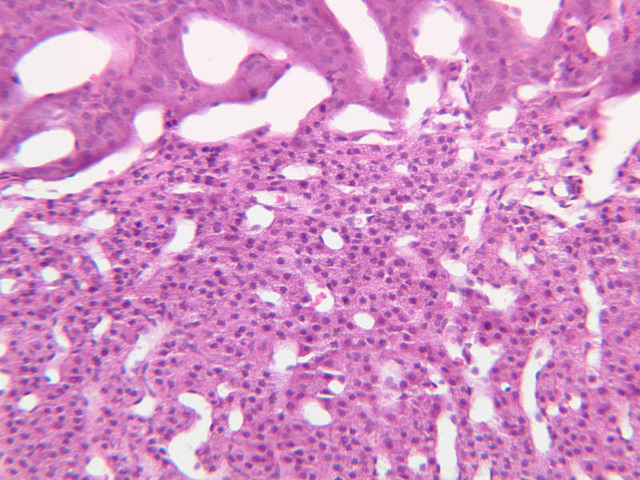

The thyroid gland (slide B-51, lead hematoxylin [10x, 20x, 40x, 40x]; B-52, H&E [10x-labeled, 20x, 40x-labeled, 40x]; B-53, PAS [2.5x, 10x, 20x, 40x]) consists of many closely packed, roughly spherical structures known as follicles, which are enclosed in a thick connective tissue capsule. Connective tissue septa extend from the capsule into the substance of the gland, carrying numerous blood vessels. Follicular cells are arranged as shells of simple cuboidal epithelium surrounding a gelatinous mass known as colloid. Look for a ring of epithelial cells around the homogeneous, pink-staining colloid. The cytoplasm of the follicular cells (principal cells) is faintly basophilic. The follicular cells secrete thyroglobulin, a glycoprotein, which is stored extracellularly in the colloid. In response to TSH, the follicular cells endocytose the colloid and hydrolyze it to form thyroxine. You can see where colloid has been resorbed because this process leaves small holes in the colloid adjacent to the follicular cells. These holes are known as resorption lacunae (B-52 [10x, 20x, 40xlabeled]). Very active follicles may exhibit a columnar epithelium and increased numbers of resorption lacunae. Between follicles, the stroma of the thyroid gland consists of a thin layer of connective tissue and a rich capillary network. Parafollicular cells (light cells or C cells) are located in the connective tissue between follicles or adjacent to follicular cells within follicles. When they lie within the follicular wall, the parafollicular cells do not reach the lumen. Parafollicular cells are slightly larger than the follicular cells and, in H & E preparations, have a more lightly stained cytoplasm (B-52, H&E [10x, 20x, 40x-labeled] [10x-labeled, 20x, 40x-labeled] [10x, 20x, 40x] [10x, 20x, 40x]; B-53, PAS [10x, 20x, 40x]). Parafollicular cells are readily identifiable in slide B-51 (stained with lead hematoxylin), where they appear as purplish-black structures in which the nuclei are difficult to discern (B-51 [10x, 20x, 40x-labeled]). These cells secrete calcitonin, which lowers serum calcium levels by inhibiting bone resorption and accelerating osteoid calcification.